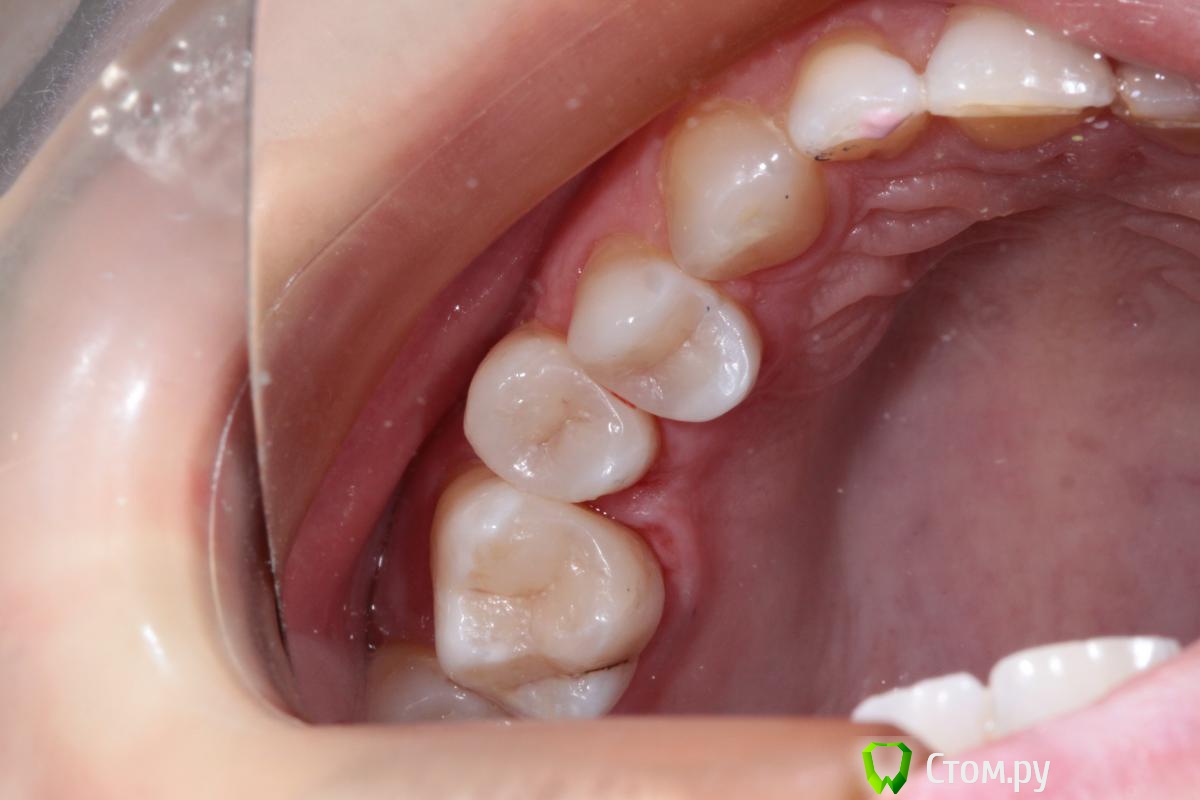

Hans85 Опубликовано 15 января, 2014 Автор Поделиться Опубликовано 15 января, 2014 Сразу скажу что с эндо у меня обстоит лучше чем с реставрациями так что сильно не пинайте.Пациентка страховая,так что речь про вкладки не идет.так сказать возможность тренится в художественной лепке.ЗУбы 26 25 24.На фото 26 уже сделанный. 7 Ссылка на комментарий

Hans85 Опубликовано 14 января, 2015 Автор Поделиться Опубликовано 14 января, 2015 для разбавления эндо чутка занимаюсь художественной лепкой,да Маэстро еще далеко,но будем учиться. 13 Ссылка на комментарий